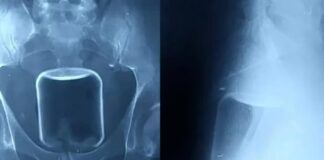

Cirurgia de emergência remove copo de vidro do intestino de homem

1 de outubro de 2024